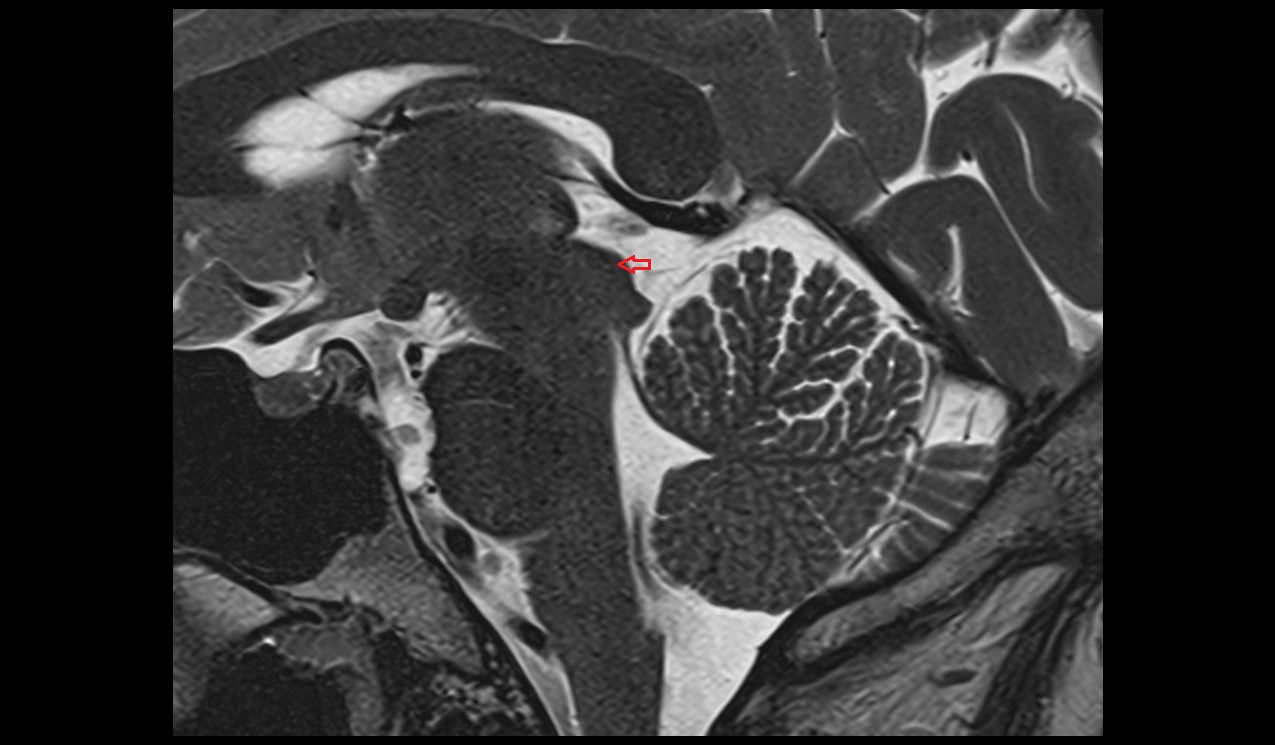

- Peripheral zone of prostate

- Anterior Fibromuscular Stroma of prostate

- Central zone of prostate

- Transitional zone of prostate